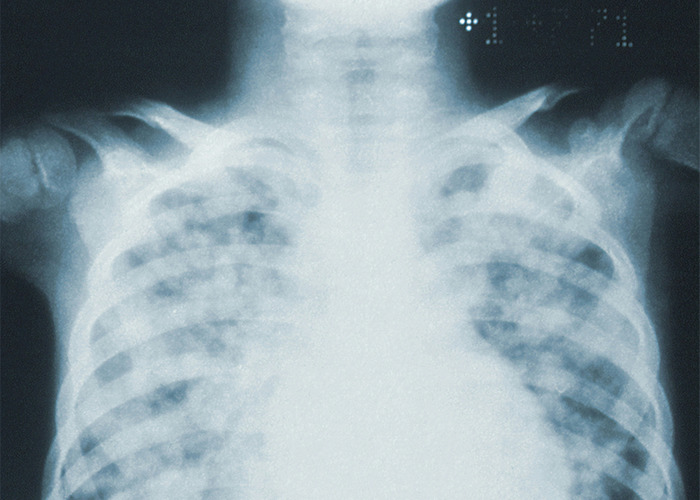

I was the patient, and the actual ER Doctors missed it (twice) "because she's too young at 22 for a pulmonary embolism". Except I was 6 months postpartum, on birth control, had recently had pneumonia and also had a family history of CVA and MI related to blood clots. I was so high risk, I was basically a DVT waiting to happen.

Thank all of the gods for putting a PA who was fresh out of school and eager to prove himself into my path....he talked the Dr into ordering a CT with contrast and they found a clot the size of a golf ball in my left lung.

The Dr was ready to discharge me, and I likely would have died if not for that PA who trusted their gut (and probably took a ration of s**t from his colleagues until he was proven correct). He knew that something wasn't adding up to simple pleurisy and saved my life by trusting his instincts.